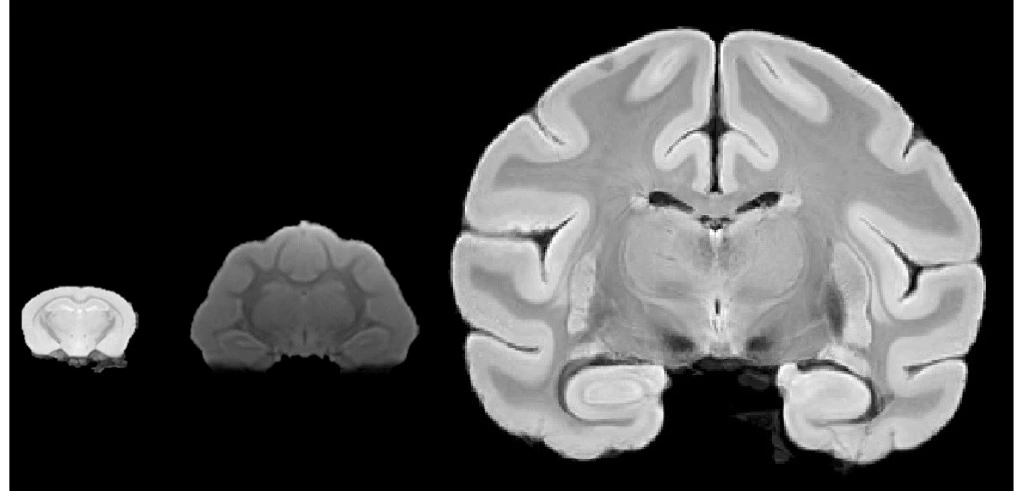

MRI microscopy of mouse, ferret and Bonnet Macaque brains. (Laurel Dieckhaus)